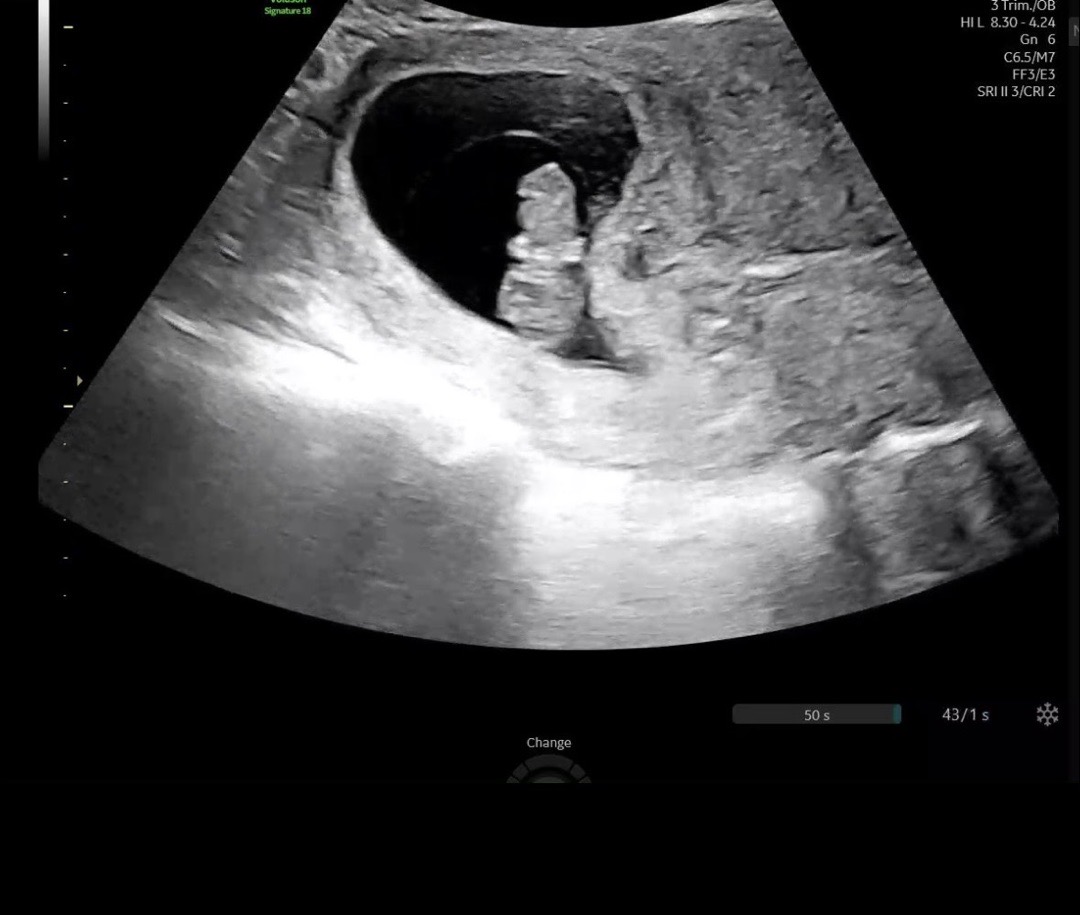

임신 9주차 젤리곰 보고왔어요!

초음파 하자마자 물구나무 서고있다고 하네요 ㅎㅎ,, 꼬물꼬물 거리는거 보고싶었는데 미동도 없이 잠만 자더라구요ㅎㅎㅎ